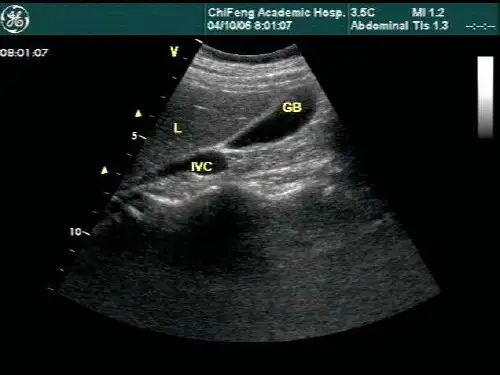

二、肝脏疾病 诊断